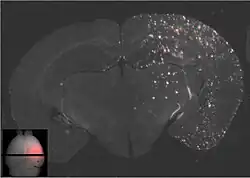

Les ultrasons peuvent être focalisés sur n'importe quel domaine du cerveau. C'est ainsi que l'on peut ouvrir la barrière hémato-encéphalique sélectivement sur des régions délimitées du cerveau. Les médicaments administrés pénétreront alors sur la zone ainsi ciblée[138]. On peut suivre le ciblage des zones par une IRM simultanée : il suffit d'administrer un produit de contraste IRM, comme du gadolinium convenablement chélaté, qui pénètre dans le cerveau à travers les parties de la barrière hémato-encéphalique ouvertes. Ces parties deviennent alors visibles en IRM. Les produits de contraste ne sont pas en mesure de franchir la barrière aux endroits où elle n'est pas ouverte.